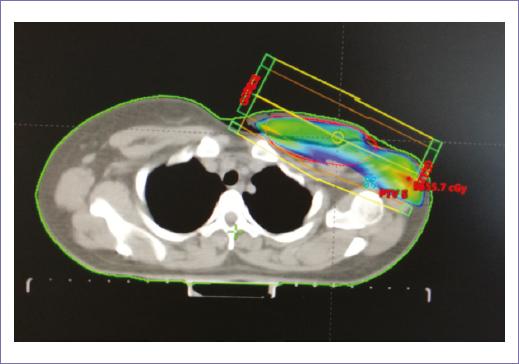

Recibió radioterapia adyuvante 50 Gy/25 fracciones, con técnica 3D conformal con campos tangenciales y axilosupraclavicular (Fig. 2); la toxicidad desarrollada durante el tratamiento fue radiodermitis grado I. Durante el seguimiento, siete meses después se documentó mediante tomografía con emisión de positrones dos nódulos pulmonares con hipermetabolismo, maximum standardized uptake value (SUVmax) 3.7 y 2.8, así como trombos en la vena pulmonar izquierda, arterias ilíacas comunes y externas. Un mes después, la paciente empezó con cefalea holocraneana con intensidad del dolor en escala visual analógica 8/10, por lo que se documentó con estudios de imagen una lesión intraaxial frontal izquierda de 50 x 42 mm, de características metastásicas (Fig. 3), motivo por lo que se consideró candidata a tratamiento quirúrgico, seguido de irradiación a holocráneo 30 Gy/10 fracciones (Fig. 4). Durante el último tratamiento presentó dificultad respiratoria súbita y se documentó tromboembolia pulmonar bilateral metastásica, motivo de fallecimiento (Fig. 5).

Figura 2 Plan de tratamiento conformal, con dos campos tangenciales y axilosupraclavicular, dosis prescrita de 50 Gy en 25 fracciones.

En relación a la radioterapia, los estudios que describen esta modalidad de tratamiento son fase II, algunos autores reportan un posible beneficio con el uso de radioterapia postoperatoria en todos los sarcomas mamarios, mientras que otros demuestran resultados contradictorios, por lo que el beneficio de la radioterapia adyuvante es controvertido15-17. La irradiación después de una resección R0 debería ser considerada de acuerdo con el riesgo de recurrencia: alto grado y tamaño mayor a 5 cm, con el objetivo de incrementar el control local. Este tratamiento después de una resección R1 está recomendado en todos los casos debido a la alta tasa de recurrencia, de hasta un 60% en algunas series. Un protocolo común es aplicar una dosis de 50-60 Gy con fracciones de 2 Gy a toda la mama/parrilla costal y posteriormente un boost (incremento de dosis) para prescribir 60 Gy al lecho tumoral. En pacientes con R2 operable se recomienda cirugía nuevamente3. En el caso que presentamos, se decidió administrar radioterapia adyuvante; por el tamaño de la lesión, el grado y el hecho de ser una recurrencia, la dosis prescrita fue de 50 Gy en 25 fracciones, con un fraccionamiento convencional, con técnica conformal de 3 campos: tangenciales y axilosupraclavicular. Finalmente, de acuerdo a la historia natural de la enfermedad la paciente presento diseminación hematógena y falleció por complicaciones pulmonares.